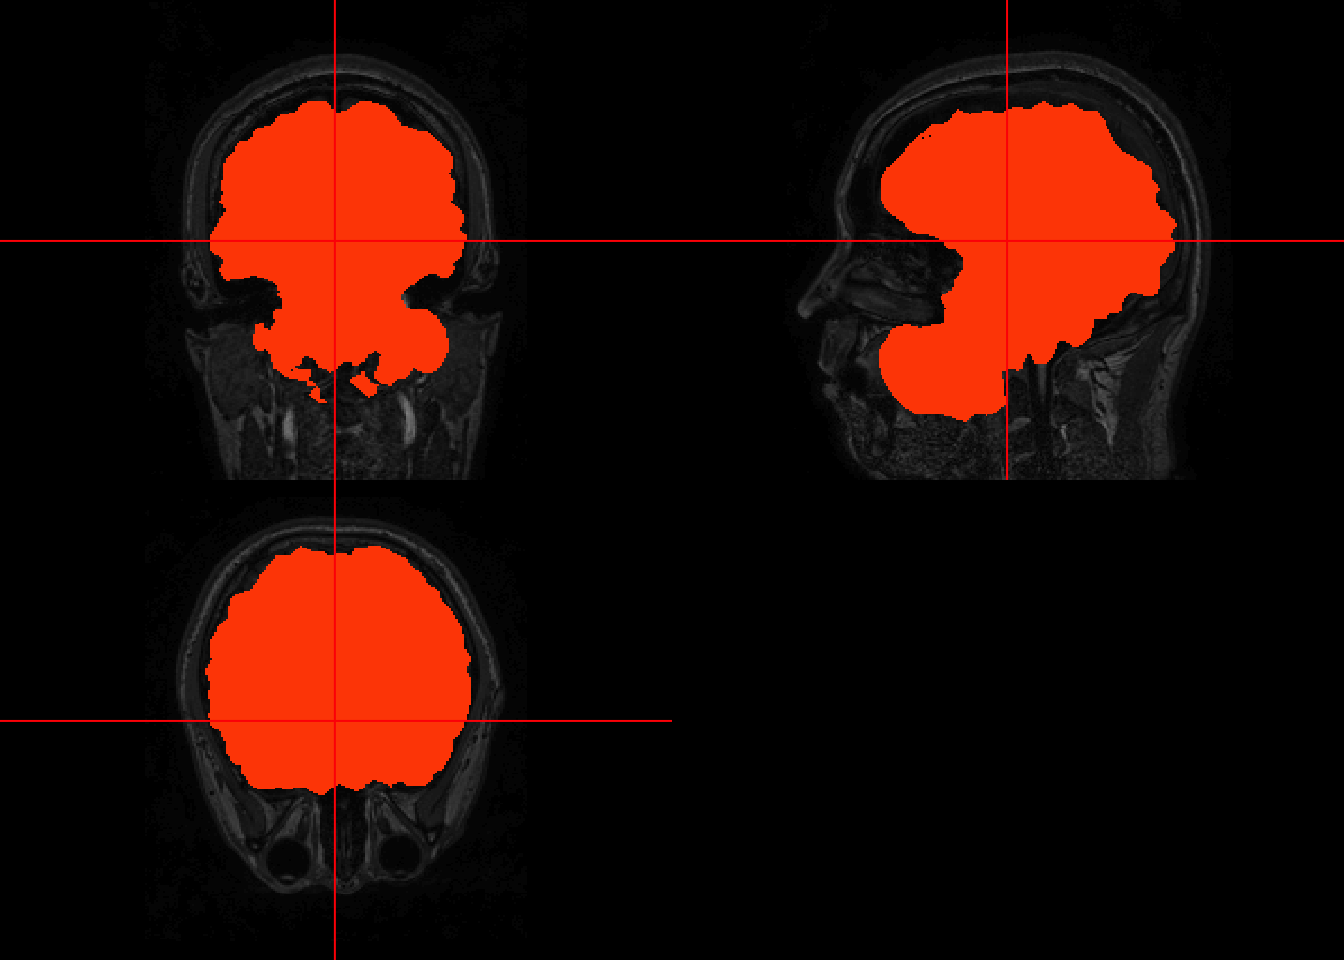

7.3 Visualizing first past

To visualize the effects of the brain extraction on the original, the orthographic may be used twice by passing (1) the image returned by BET, (2) the original image overlaid by a mask. To produce the mask, follow the code below.

# create an array of 1s with same dimensions as the skull-stripped image

bet_fast_mask = niftiarr(bet_fast, 1)

# set all non-brain voxel to NA

bet_fast_mask[!(bet_fast > 0)] <- NA

# plot

orthographic(bet_fast)

The results are not great since a lot of non-brain areas get included.